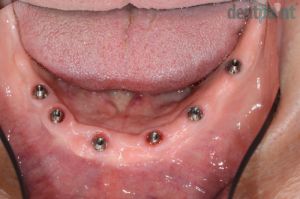

Kivehető implantációs fogpótlás

Implantátumokra rögzített, kivehető fogsor. Páciensünk arcprofilja javult, a rögzített fogsoroknak köszönhetően az ételek megrágása újból akadálytalan és hatékony!

1) Kiindulási helyzet

2) Gyógyult implantátumok

3) Elkészült kivehető fogpótlás

4) Elégedett mosoly